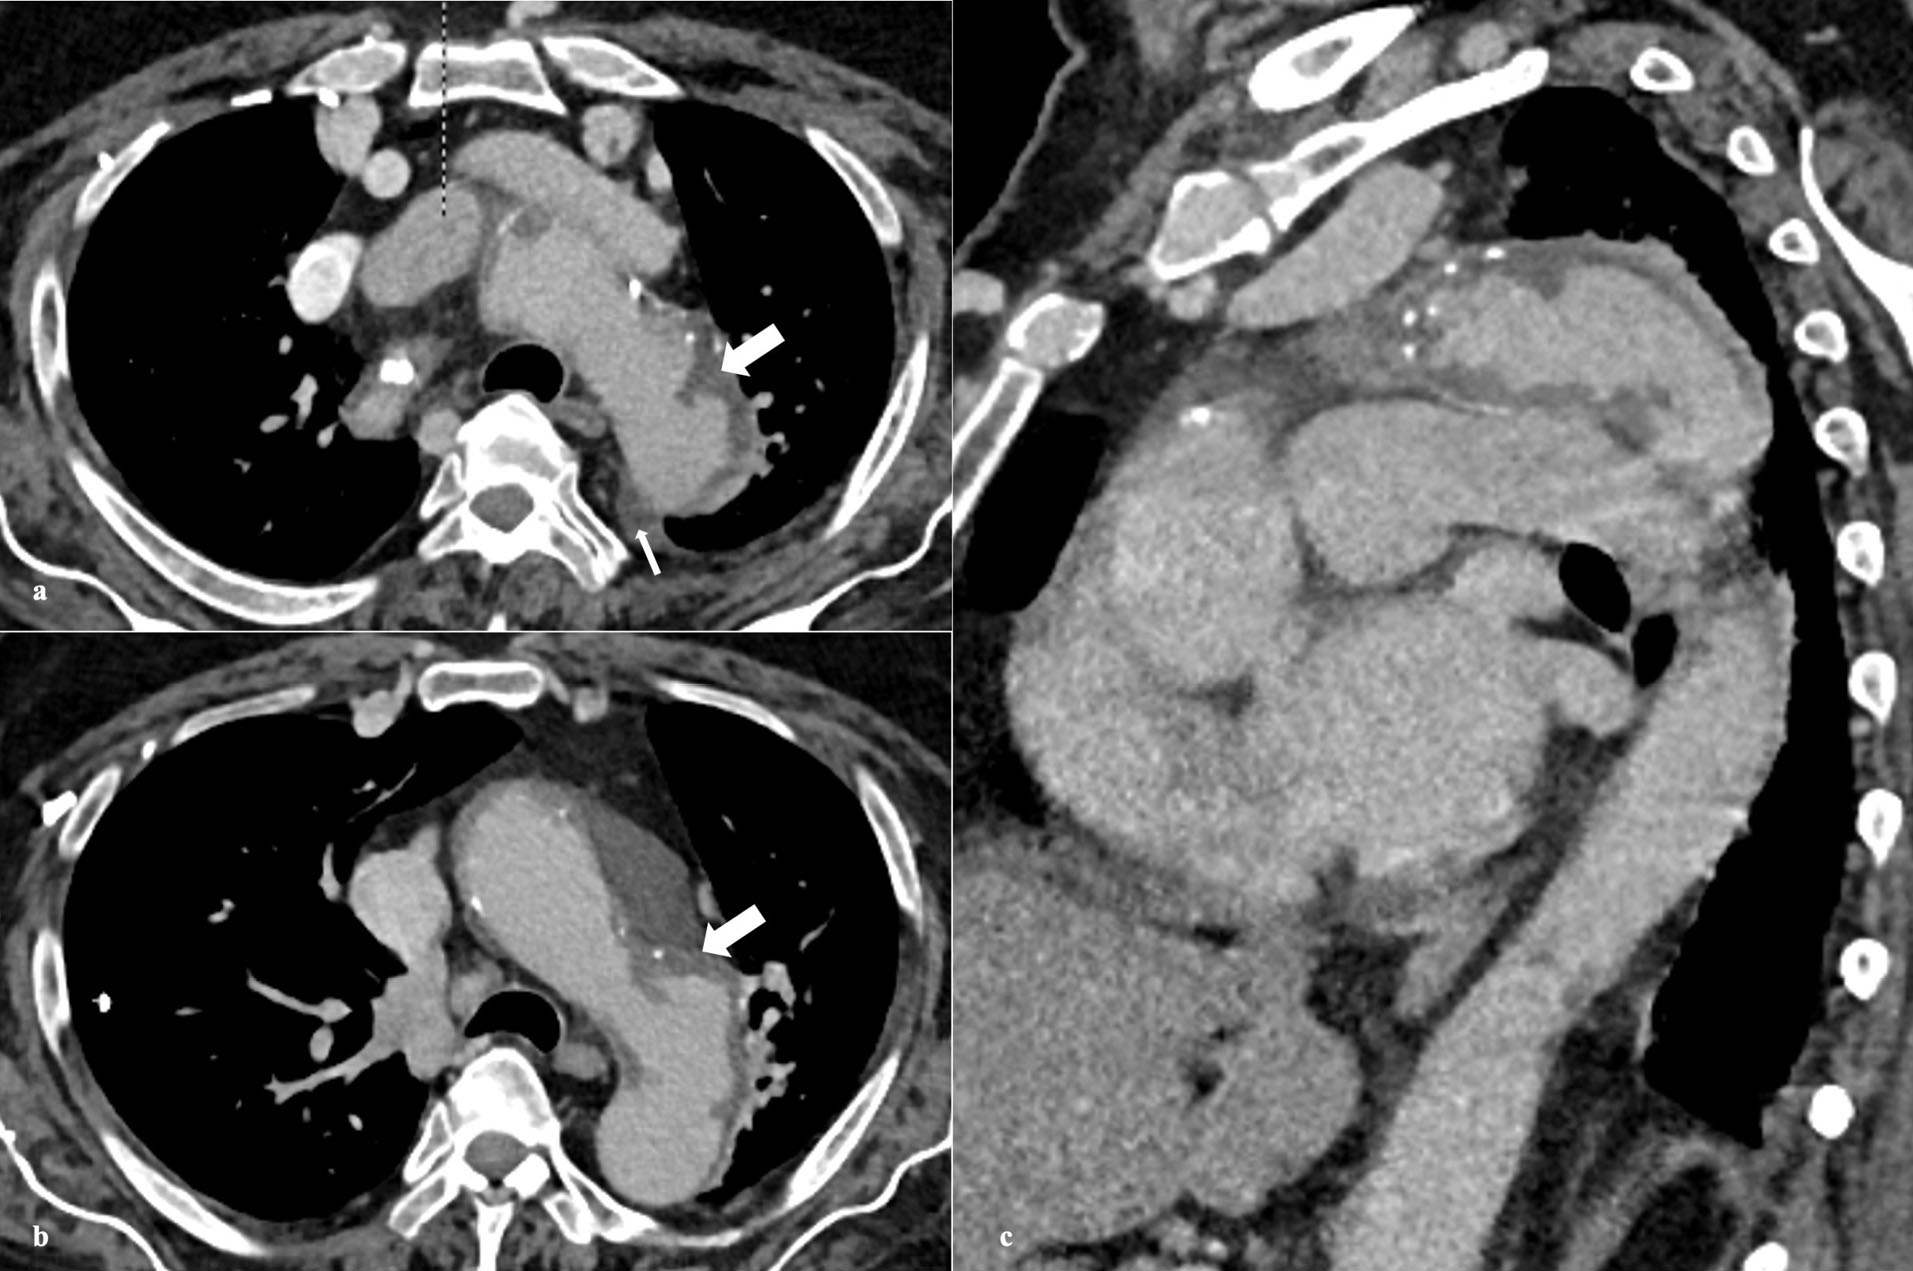

PAU is seen on CTA as contrast filled outpouching (, ) or crater-like morphology on aortography and TEE.

4,6,56

There is invariable surrounding IMH and medially displaced calcified intima ().

Figure 1.

Axial plain (a) CT image shows calcified atherosclerotic wall calcification. Axial arterial phase (b,c,d) CT images reveal multiple contrast-filled outpouchings arising along all walls of the aorta, suggesting penetrating atherosclerotic ulcer

Figure 2.

Coronal (a,b) and Sagittal (c,d) multiplanar reconstructed arterial phase CT images depict the true extent of penetrating atherosclerotic ulcers

Figure 3.

Axial (a) and Sagittal (b,c) contrast-enhanced CT images reveal penetrating atherosclerotic ulcers involving aortic arch with associated intramural hematoma (thick arrow) and small effusion (thin arrow)